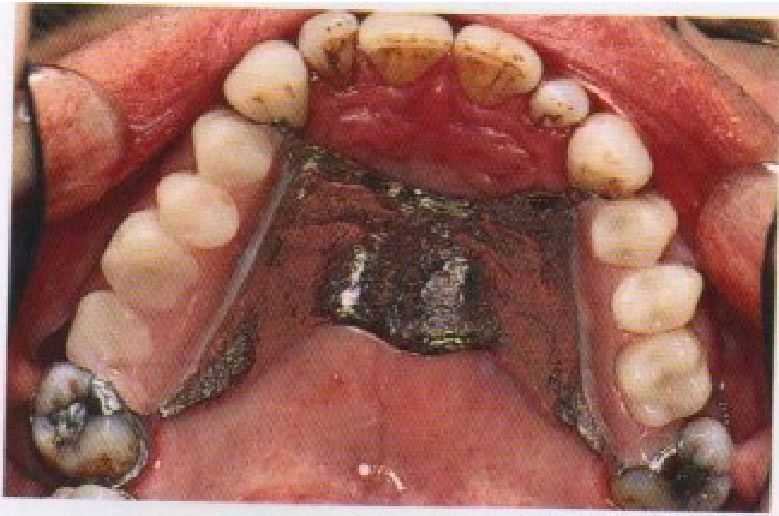

Рис. 2-3. Использование частичного съемного протеза для эффективного замещения двух включенных дефектов в боковых отделах верхнего зубного ряда. Рис. 2-4. Использование частичного съемного протеза для восстановления сочетанной потери передних и боковых зубов.

следние показаны при сочетании дефектов зубного ряда в переднем и боковых отделах в случае потери значительного количества передних и боковых зубов. Их выгодное свойство одновременно замещать различные дефекты продемонстрировано на рис. 2-4.